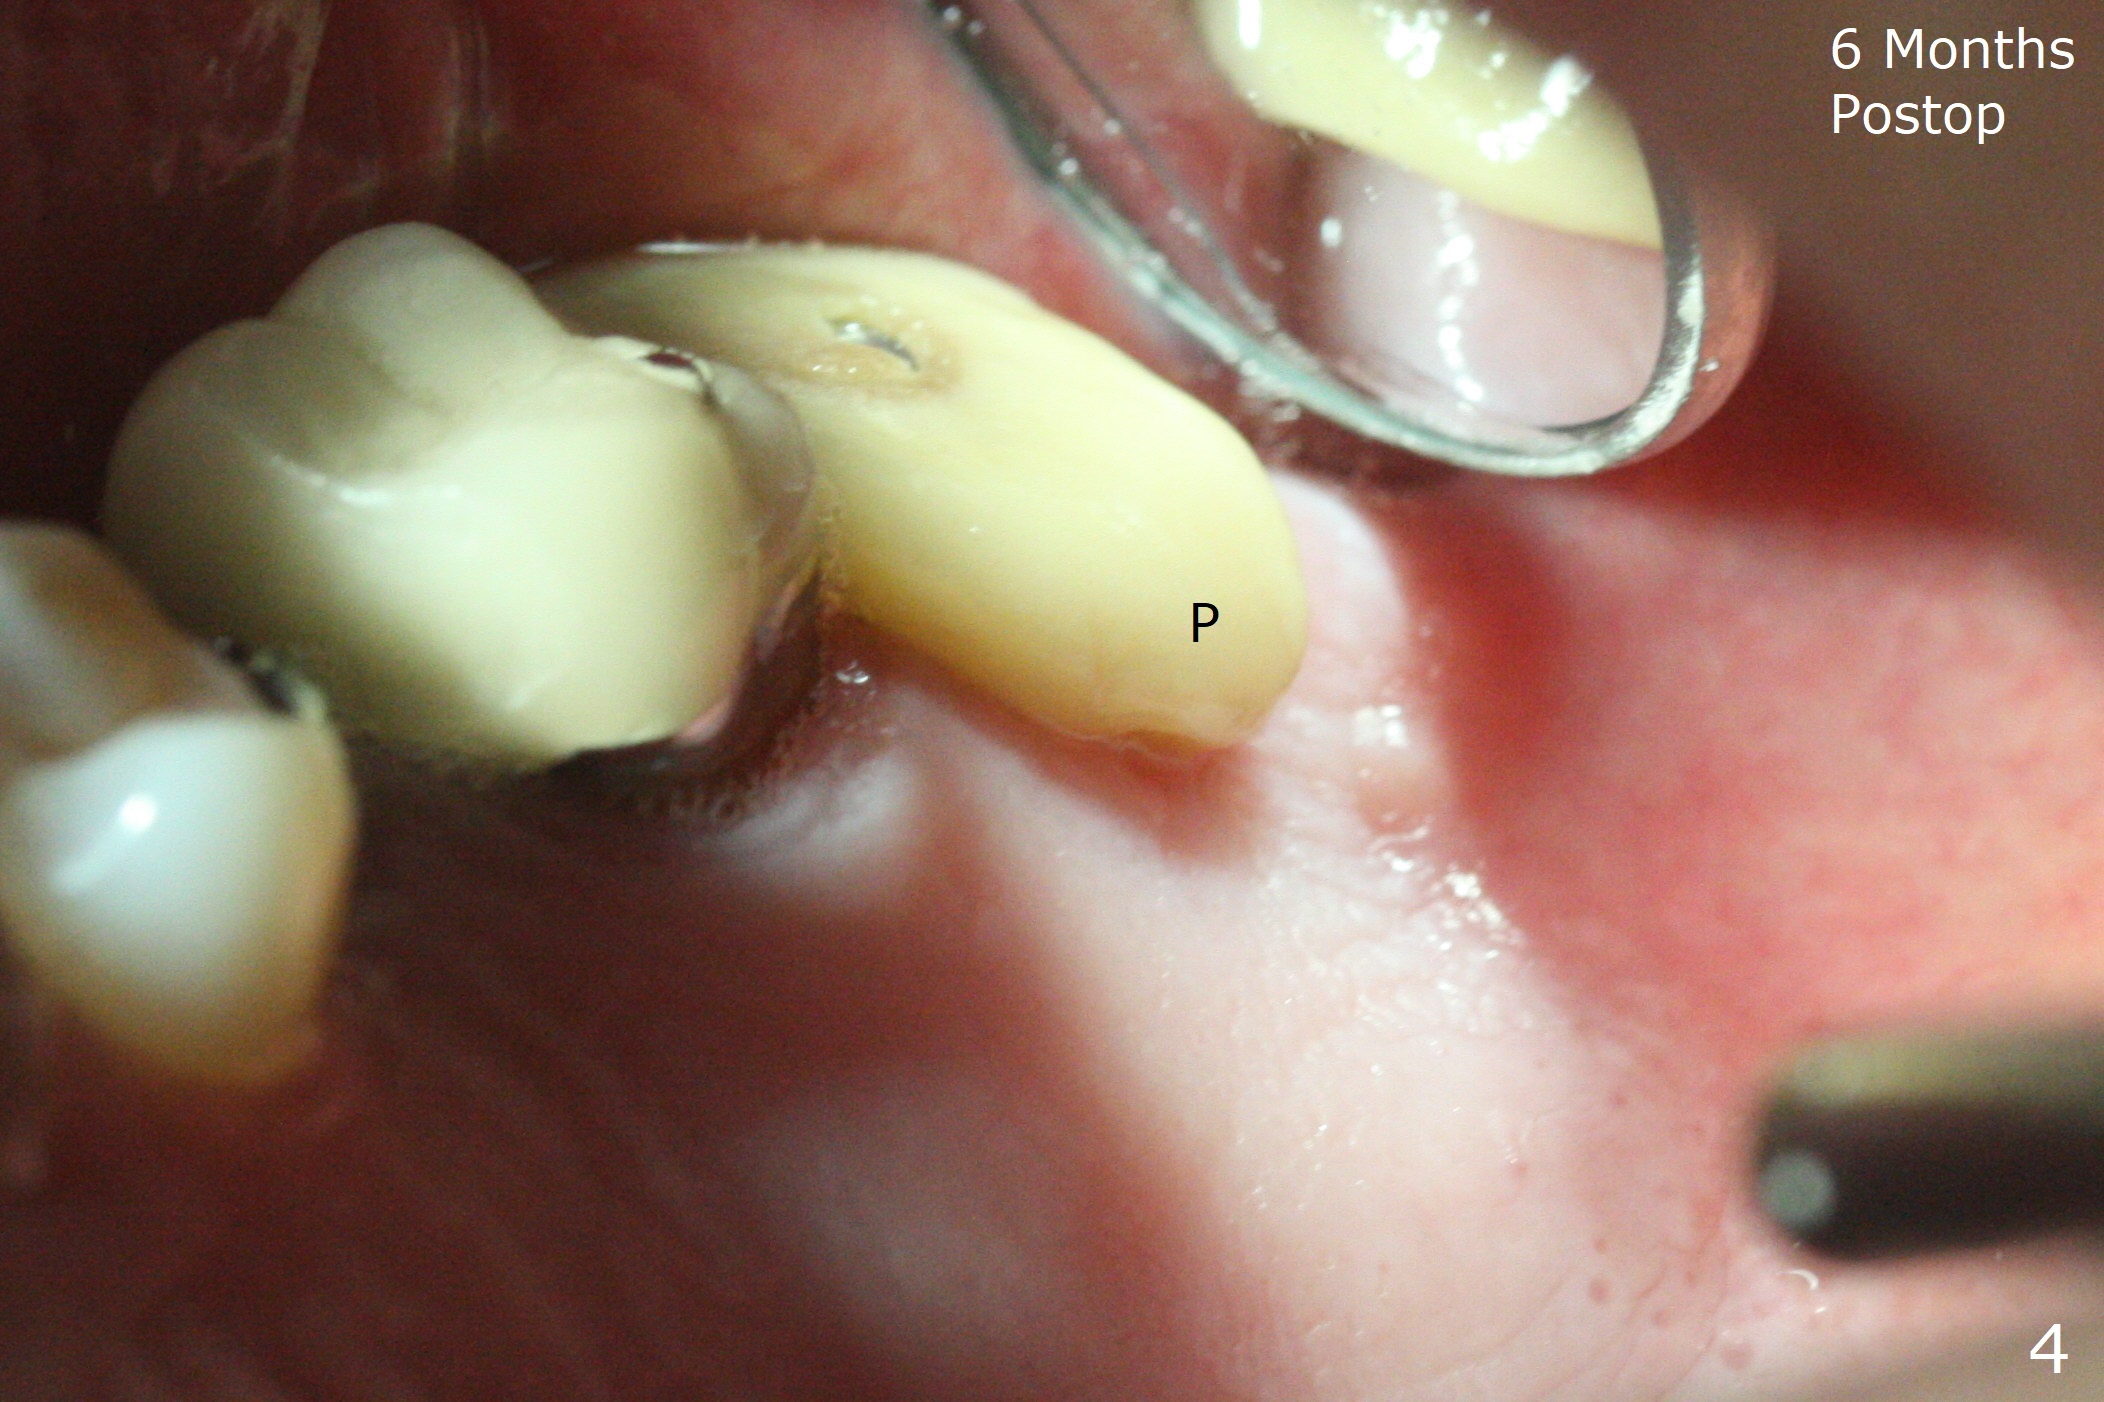

The palatal gingival margin of the tooth #15 with vertical root fracture is low, consistent with the low palatal plate after extraction (Fig.1 >). With IS guide, a 5x11 mm IBS implant is placed in the septum with >5 mm the palatal gap. After underprep in depth, a 3.5x9 mm achieves primary stability (Fig.2,3). The palatal defect is repaired with allograft (*) and 2 pieces of PRF membrane. The palatal soft tissue defect appears to have been repaired 6 months postop (Fig.4,5). When a narrower abutment with longer cuff is placed at #15 (6x4(4) mm in Fig.6, as compared to 6.5x4(3) mm one in Fig.2), there is no gap between the implant and abutment. In contrast there is one at #13 (Fig.6 <) when a 4x4(4) mm abutment is seated following removal of a 4x4 mm healing abutment. After use of a 4.6 mm profile drill, the gap disappears (Fig.7). Impression is taken.